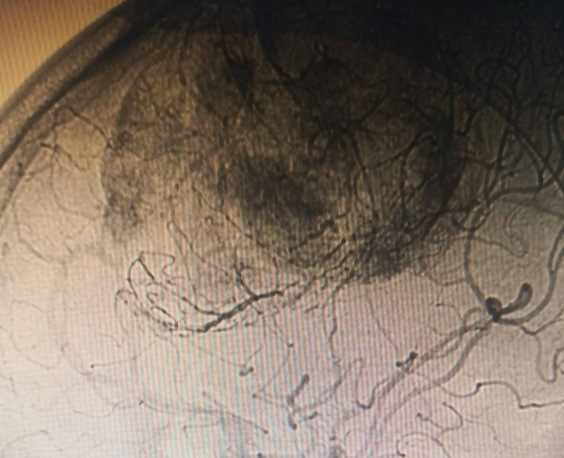

神经外科血管介入组曲友直副教授、崔刚副教授和高攀主治医师对肿瘤进行了瘤栓塞治疗,有效减少了肿瘤的血供,为后续的手术切除降低了风险。栓塞治疗后,神经外科王睿智副主任、高李贵副教授和董全主治医师在麻醉科、心内科、输血科等科室的全力配合下,凭借精湛的医术和丰富的临床经验,成功为患者切除了病变。手术过程中,麻醉科吕建瑞主任团队全程监控患者的生命体征,确保麻醉安全;心内科团队随时准备应对可能出现的心脏问题;输血科团队则确保充足的血液供应,以备不时之需。多学科的通力合作,为手术的成功提供了坚实的保障。